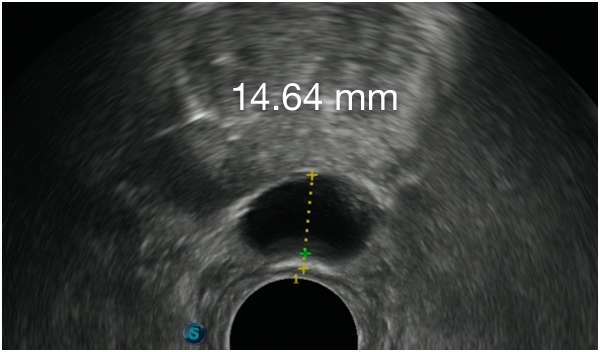

Barrigelの初回留置-連続症例(同日内)

TRUS画像提供:Daniel R. Welchons, MD

Urologist; New York, United States

DR. WELCHONSの留置テクニック